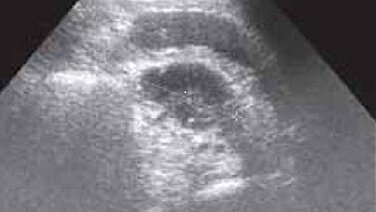

УЗИ-диагностика при абсцессе брюшной полости.

Абсцесс брюшной полости – наличие в брюшной полости гнойника, ограниченного пиогенной капсулой, образующейся вследствие защитной реакции организма, чтобы изолировать гной от здоровых тканей. По месту локализации в брюшной полости абсцессы делят на: Ретроперитонеальные и интраперитонеальные абсцессы могут располагаться в районе анатомических каналов, сумок, карманов брюшной полости, а также в клетчатке брюшины. Интраорганные абсцессы формируются в паренхиме печени, селезенки или на стенках органов...